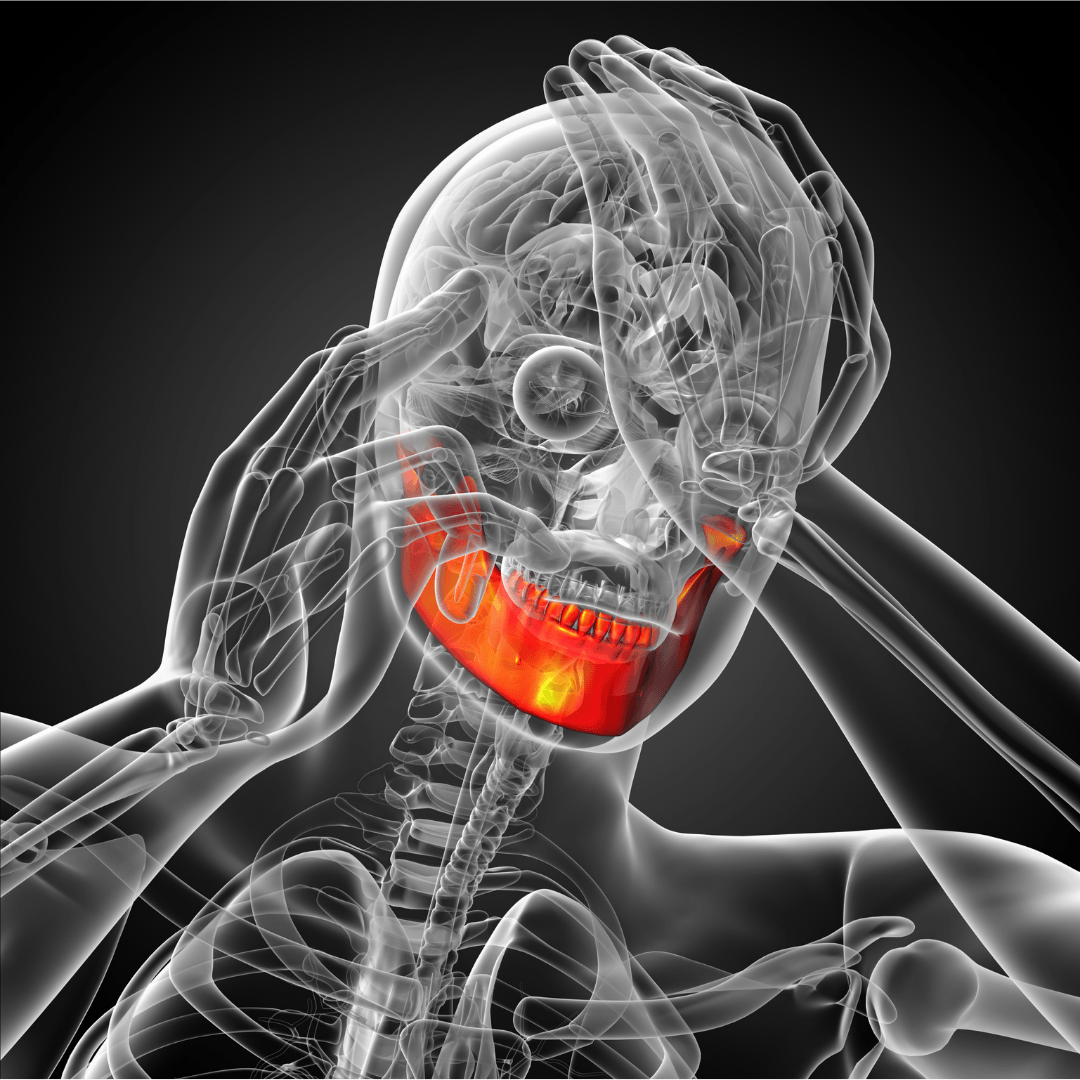

DISFUNCIÓN CERVICOMANDIBULAR

La disfunción cervicomandibular y el dolor orofacial son condiciones que afectan a la articulación temporomandibular y a la región cervical. Se basan en un desequilibrio en la función y la estructura de estas áreas, lo que puede resultar en dolor, dificultad para abrir o cerrar la boca, chasquidos o crepitación en la mandíbula, dolores de cabeza y molestias en el cuello.

Estas condiciones pueden ser causadas por factores como el estrés, la mala postura, el bruxismo o la lesión traumática. El tratamiento de la disfunción cervicomandibular y el dolor orofacial se basa en enfoques multidisciplinarios.

TALLER: BIOMECÁNICA DE LA ATM Articulación Temporomandibular

La articulación temporomandibular ATM, conecta el cráneo con la mandíbula y genera un movimiento de bisagra unido a movimientos deslizantes, protegidos por un pequeño menisco. En este taller hablaremos de la mecánica articular de esta compleja articulación causante de un porcentaje elevado de dolor.

TALLER: EJERCICIOS PARA LA ARTICULACIÓN TEMPOROMANDIBULAR

La ATM es una articulación que genera dolor en un porcentaje elevado de personas, ya sea por desgaste del menisco interno, por artritis, artrosis, por causa traumática, luxación, activación de puntos gatillo musculares, etc. En este taller práctico, veremos algunos ejercicios y técnicas que pueden ayudarnos a liberar tensiones y a recuperar la movilidad y el espacio interarticular.

Montse Herrero (fisioterapeuta y PNIE)

Master-D Provenza 112 BARCELONA